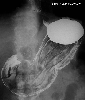

A case of type 2 advanced gastric cancer involving the lower esophagus.

X-ray